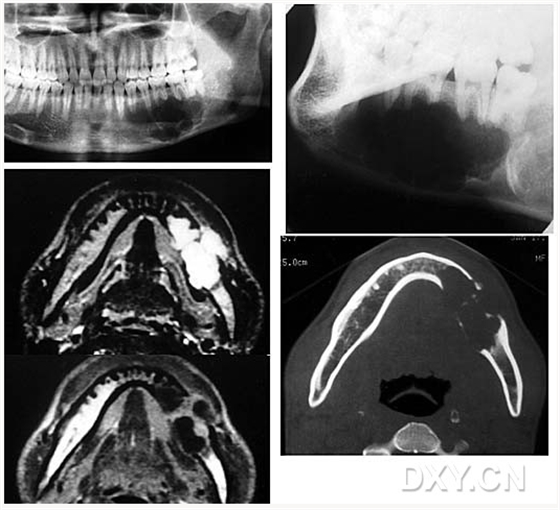

成釉細(xì)胞瘤

鼻鄂囊腫

根尖囊腫

骨肉瘤